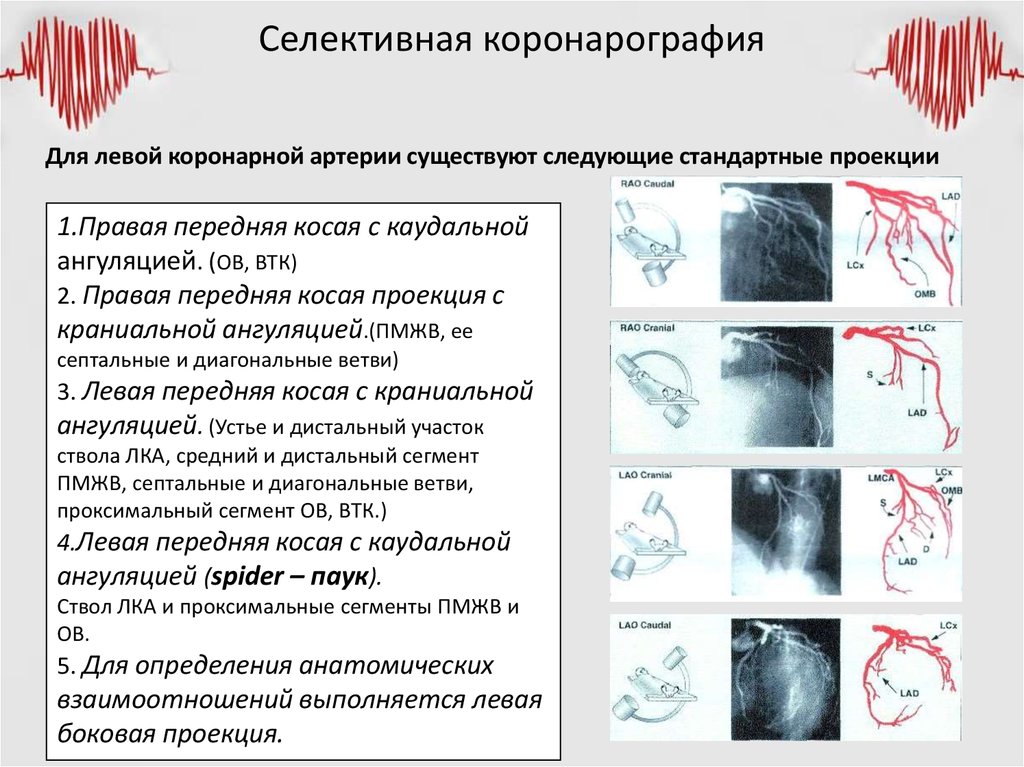

Коронарография сердца: доступы, техника пункции артерий и основные этапы исследования

Коронарография

КОРОНАРОГРАФИЯ СОСУДОВ ЛЕВОЙ СЕРДЕЧНОЙ АРТЕРИИ